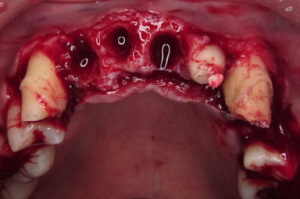

歯槽膿漏を手術によって審美的にした症例

初診です。

全体的に中程度の歯槽膿漏です。

そのせいで葉の長さがまちまちになっています。

全ての不良の被せ物を外して仮歯にします。

同時に根の治療と矯正、インプラント埋入を

行いました。

この写真は向かって左上の前歯2本を

矯正しています。

仮歯で隠して行っています。

矯正終了後、歯槽膿漏の除去の為、

歯周手術を施します。

前の部分は歯茎をずらすように縫合し

奥歯は移植を行っています。